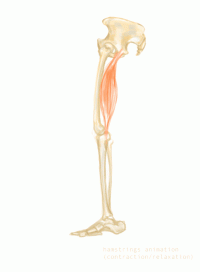

腘绳肌包括大腿后部的三块肌肉:股二头肌、半腱肌和半膜肌。这些肌肉都由坐骨神经支配。作用有两个:伸髋和屈膝。hamstring,其中ham指的是腘窝,即膝关节后面的凹陷,string指的是位于该部位的肌腱。

图一:腘绳肌解剖